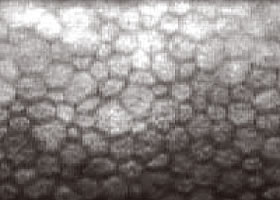

ダメージを受けた角膜内内皮細胞

角膜内皮細胞の死滅減少→角膜の混濁[水疱性角膜症]→視力低下

継続的に酸素不足が続くと、角膜の細胞が死んでしまい、一度失った細胞は再生されることはありません。

また残っている細胞も大きさや形にばらつきが出てしまいます。